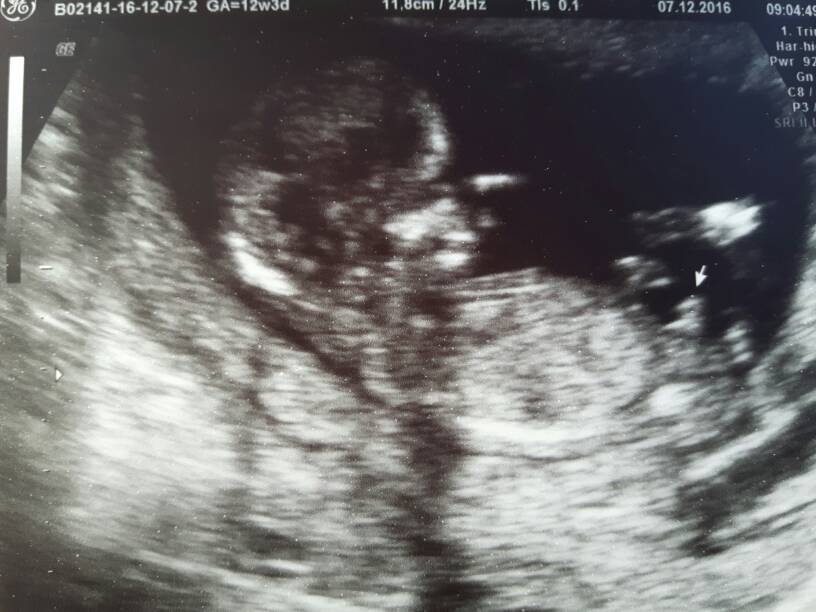

Wspaniale, gratulujęKochane wszystko super. Dzidzia łapała się w samym środku norm. Cudowne uczucie zobaczyć maluszka. Machał nam i ssał paluszka na 80 % chłopak . To już będę mieć dwóch [emoji23][emoji4][emoji4]Zobacz załącznik 786556 Zobacz załącznik 786557

Gratulacje! Przepiękny Synuś <3Kochane wszystko super. Dzidzia łapała się w samym środku norm. Cudowne uczucie zobaczyć maluszka. Machał nam i ssał paluszka na 80 % chłopak . To już będę mieć dwóch [emoji23][emoji4][emoji4]Zobacz załącznik 786556 Zobacz załącznik 786557